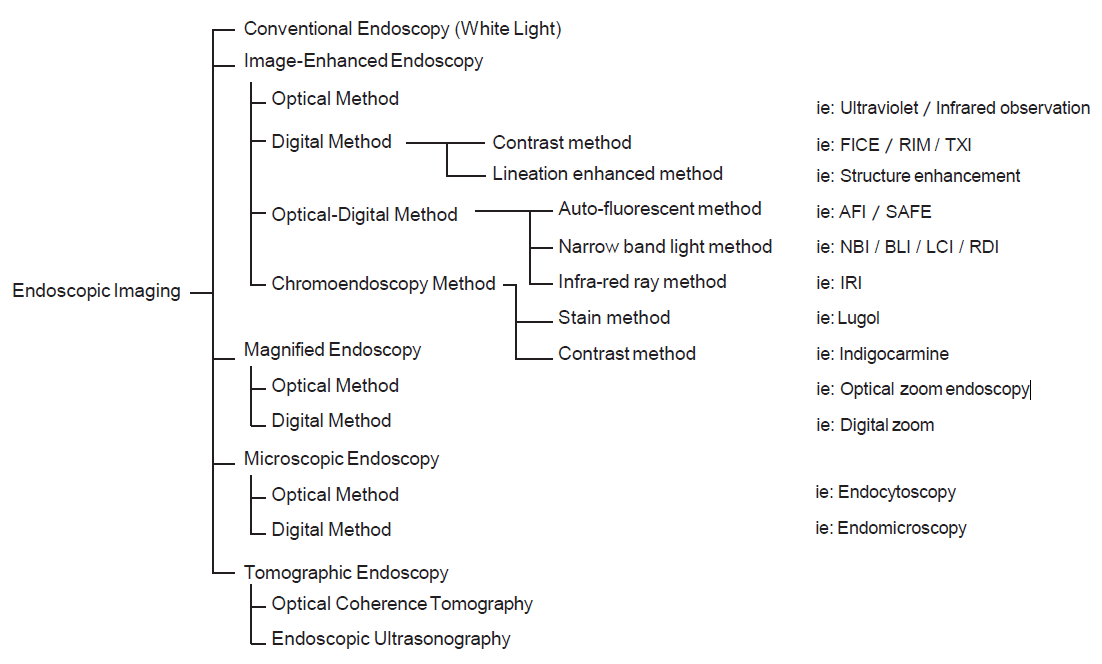

Between the late 1980s and early 1990s, research on image processing and analysis was conducted mainly by the National Cancer Center Hospital East and Olympus Group, which led to basic experiments on narrow band light imaging starting in 1994. As a result, a patent application was made in 1999, and a narrow band imaging (NBI) device (Olympus Co., Tokyo, Japan) was introduced commercially in 2006. Since the early 2000s, it has been demonstrated by a number of researchers that NBI is useful for early diagnosis of cancers of the oropharynx, hypopharynx, esophagus, stomach, and large intestine. A succession of similar techniques was later made public, and interpretation of the term “special light observation” began to differ among academic societies and research organizations. In view of this problem and the need to establish internationally applicable terminology for endoscopy, we proposed an object-oriented classification for endoscopic imaging in 2008. Basically, the concept was that endoscopic imaging can be divided into five categories: (1) conventional endoscopy (white light endoscopy (WLE)), (2) image-enhanced endoscopy (IEE), (3) magnified endoscopy, (4) microscopic endoscopy, and (5) tomographic endoscopy [1].

IEE is subdivided into optical, digital, optical-digital, and chromoendoscopy methods.

Since the introduction of this classification, several IEE techniques have become commercially available through advances in endoscopy technology, including blue light imaging (BLI), linked color imaging (LCI), red dichromatic imaging (RDI), and texture and color enhancement imaging (TXI). Therefore, a revised version including those techniques is presented in Fig. 1.